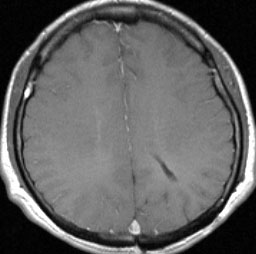

central neurocytomaが透明中隔 septum pellucidum から発生していることがよくわかる症例です。症状はありませんでしたが,この腫瘍がこのままのサイズで留まることはあり得ないので手術摘出を勧めました。これ以上大きくなると手術にしても放射線治療にしてもリスクが大きくなりすぎます。脳弓にくっつくので脳弓損傷を避けるのが手術のポイントです。脳室壁にくっつくのですが剥がしていけば取れますが,大きな上衣下静脈 large subependymal vein の損傷には注意を払います。

手術後の画像です。脳神経外科の先生は手術根 surgical track に注目して下さい,左頭頂葉皮質切開 transcortical approachで手術を行っています。このルートでは全く手術後の神経脱落症状が出ませんでした。central neurocytomaの手術方法は,上記に加えて前頭葉皮質切開でまっすぐ前角に入る方法と経脳梁法 transcallosal approachがあります。経脳梁法は限られた小さめの腫瘍にしか応用できません。anterior callosal approach以外ではdisconnection syndromeが出るからです。central neurocytomaは脳室の壁にベトベトくっつくし,anterior callosal approachでは脳室壁の観察はかなり限られるからです。大きなものでは必ず経皮質法を選択して下さい。